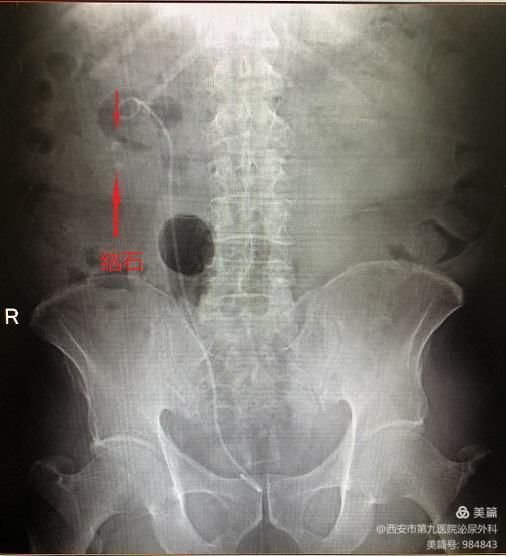

75岁男性患者张某,因右侧肾绞痛在泌尿外科诊断为右肾多发结石(4枚),于2月于在科室行右肾结石输尿管软镜下钬激光碎石术,术后已康复出院

术前结石如上图,右肾多发结石